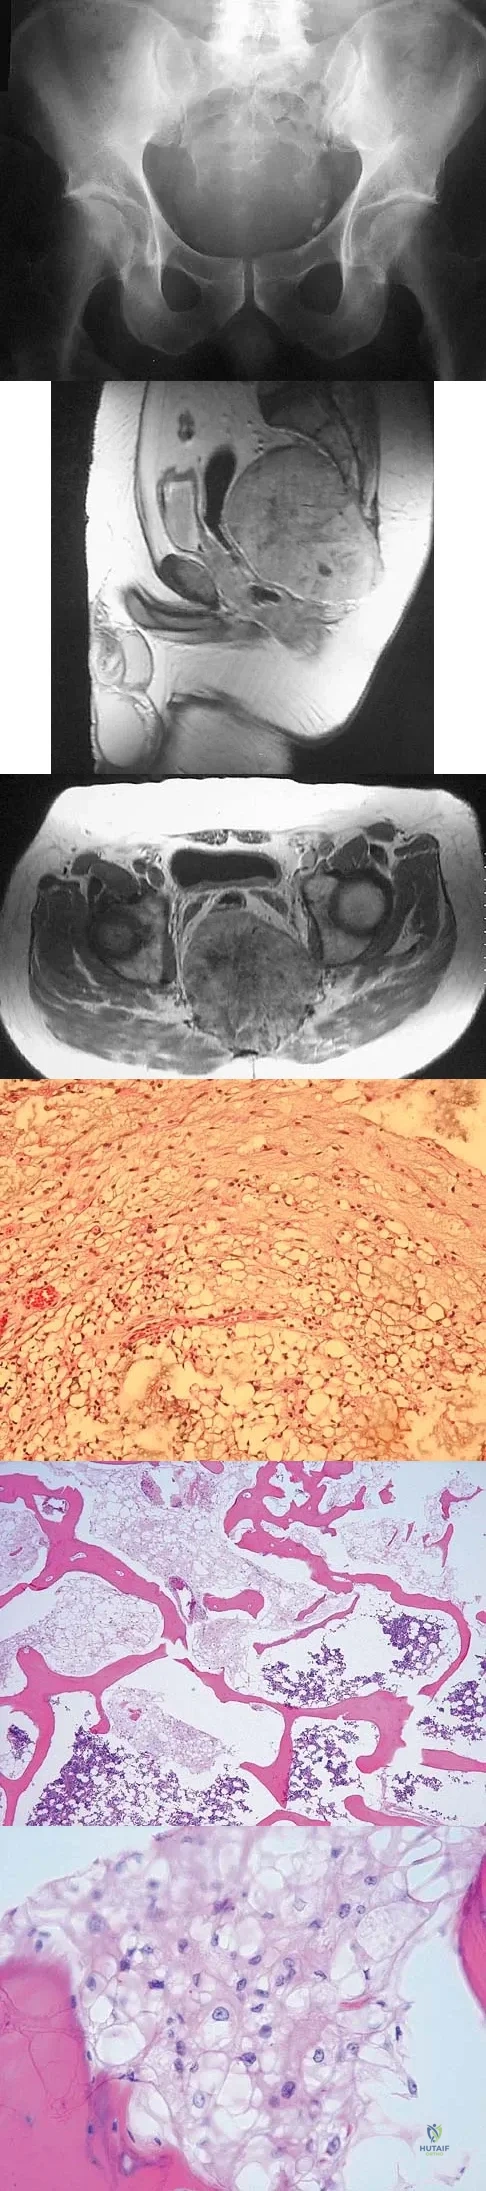

The biopsy specimens seen in Figures 55a and 55b are from a lytic lesion in the sacrum of a 58-year-old man. What is the most likely diagnosis?

Explanation